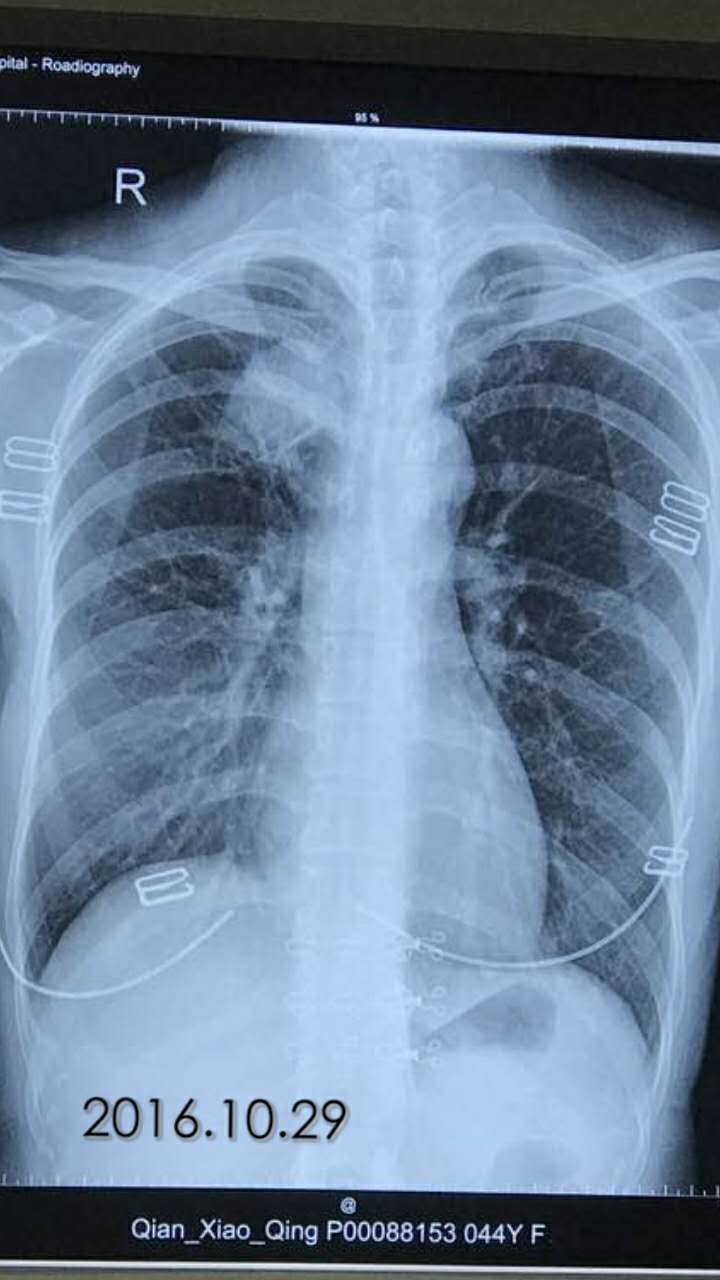

陈医生,这是2016.10.26的ct看看拍的对不

举报

2017-10-31 10:10:21 有用(0)

回复(0)